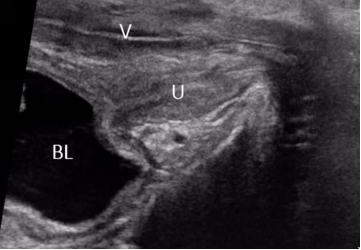

▶ 1、经直肠或经阴道途径:可应用双平面腔内探头或者腔内端射式探头进行检查,应用双平面腔内高频探头扫查时可获得尿道正中矢状切面及横切面。

▶ 1、静息状态:可观察尿道形态、走行、回声是否正常、前后壁是否连续等,并进行相应测量;可对尿道占位性病变进行评估。

▶ 2、排尿状态:主要观察尿道通畅性、腔面连续性、光滑度、尿液流出路径以及尿道腔内情况。一般应用于尿瘘、尿道狭窄、尿道憩室、尿道结石、尿道腔内病变等疾病的评估。